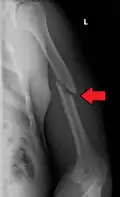

Midshaft humerus fracture with callus formation

Middle

Middle fractures are usually caused by either physical trauma or falls. Physical trauma to the humerus shaft tends to produce transverse fractures whereas falls tend to produce spiral fractures. Metastatic breast cancer may also cause fractures in the humerus shaft.[12] Long spiral fractures of the shaft that are present in children may indicate physical abuse.[5]

Definitive diagnosis of humerus fractures is typically made through radiographic imaging. For proximal fractures, X-rays can be taken from a scapular anteroposterior (AP) view, which takes an image of the front of the shoulder region from an angle, a scapular Y view, which takes an image of the back of the shoulder region from an angle, and an axillar lateral view, which has the patient lie on his or her back, lift the bottom half of the arm up to the side, and have an image taken of the axilla region underneath the shoulder.[9] Fractures of the humerus shaft are usually correctly identified with radiographic images taken from the AP and lateral viewpoints.[12] Damage to the radial nerve from a shaft fracture can be identified by an inability to bend the hand backwards or by decreased sensation in the back of the hand.[5] Images of the distal region are often of poor quality due to the patient being unable to extend the elbow because of pain. If a severe distal fracture is suspected, then a computed tomography (CT) scan can provide greater detail of the fracture. Nondisplaced distal fractures may not be directly visible; they may only be visible due to fat being displaced because of internal bleeding in the elbow.[7]

Fractures of the humerus are classified based on the location of the fracture and then by the type of fracture. There are three locations that humerus fractures occur: at the proximal location, which is the top of the humerus near the shoulder, in the middle, which is at the shaft of the humerus, and the distal location, which is the bottom of the humerus near the elbow.[9] Proximal fractures are classified into one of four types of fractures based on the displacement of the greater tubercle, the lesser tubercle, the surgical neck, and the anatomical neck, which are the four parts of the proximal humerus, with fracture displacement being defined as at least one centimeter of separation or an angulation greater than 45 degrees. One-part fractures involve no displacement of any parts of the humerus, two-part fractures have one part displaced relative to the other three; three-part fractures have two displaced fragments, and four-part fractures have all fragments displaced from each other.[13][14][3] Fractures of the humerus shaft are subdivided into transverse fractures, spiral fractures, "butterfly" fractures, which are a combination of transverse and spiral fractures, and pathological fractures, which are fractures caused by medical conditions.[12] Distal fractures are split between supracondylar fractures, which are transverse fractures above the two condyles at the bottom of the humerus, and intercondylar fractures, which involve a T- or Y-shaped fracture that splits the condyles.[7]

Fractures of the humerus shaft are most often uncomplicated, closed fractures that require nothing more than pain medicine and wearing a cast or sling. For midshaft fractures up to 12 weeks may be required for healing.[17]